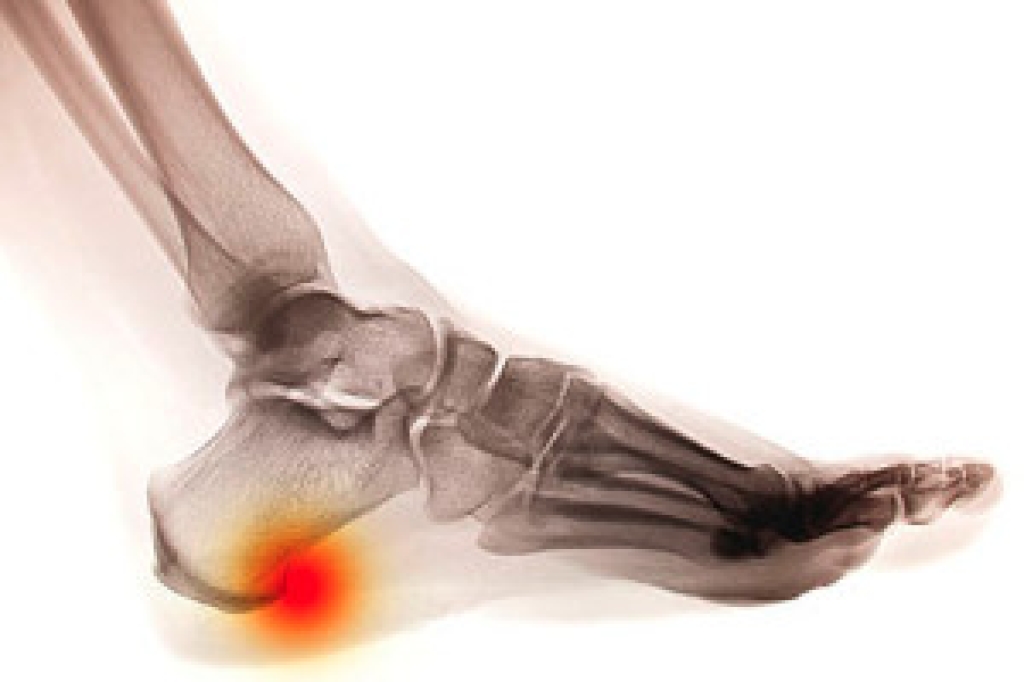

People who wear custom orthotics often experience improved posture, less joint strain, and greater endurance during work, exercise, and leisure activities. The support they provide helps relieve chronic discomfort from conditions such as plantar fasciitis, flat feet, and heel pain, while also reducing the risk of future injuries. For those who stand for long hours or engage in sports, orthotics can make movement smoother and more efficient, allowing the body to perform at its best without unnecessary stress.